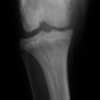

術前側面像

術前正面像

術後側面像

術後正面像

術前に25°であったTPAは、TPLO実施により7°に矯正されました。症例の歩行状態は良好です。